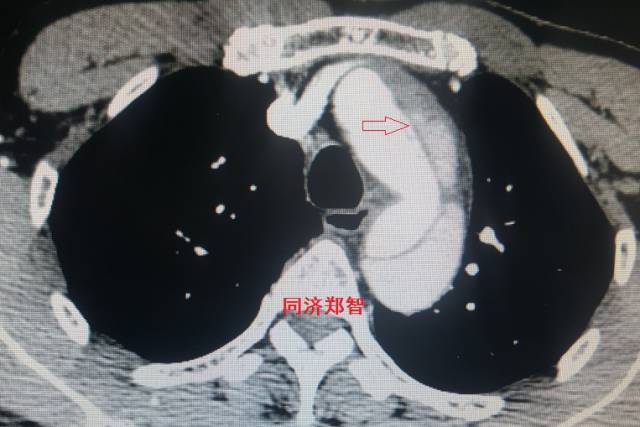

病例六

平扫CT提示降主动脉内膜片影(白箭头所示),CTA显示为B型主动脉夹层。